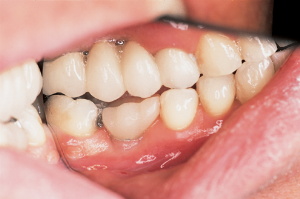

A 55-year-old male patient presented to our clinic seeking replacement of his lower left first molar. The patient’s medical and dental history was obtained in the usual manner. The history revealed a healthy male with good oral hygiene, with no contraindications to implant treatment. His major concern was to avoid conventional bridging, which required the removal of sound tooth structure. He was not very happy with a conventional bridge on the opposing arch, because of the tooth destruction and the inability to clean the area easily. He stated, "Had I known about implants earlier, I would have never consented to a conventional bridge procedure." The Internet was his source of implant information, not his previous dentist.

During the initial visit, study models and a periapical radiograph were obtained.A physical/visual examination was also performed to determine buccal-lingual alveolar bone dimension. With this information and a radiograph overlay implant selector (BASIC Dental Implant Systems), a 4-mm by 15-mm implant was selected for placement (Figure 1).A clear acrylic surgical stent was fabricated to guide the osteotomy drills (Figure 2).